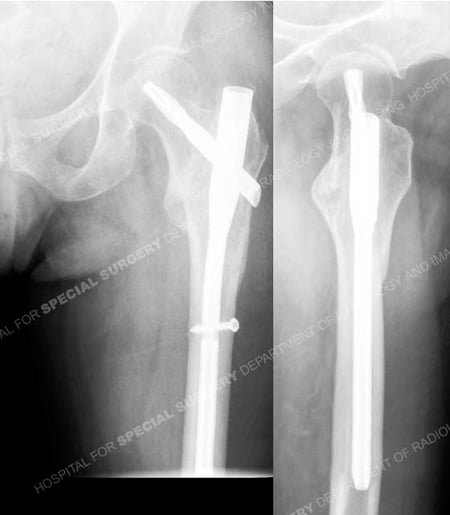

Anteroposterior and lateral radiographs 6 months following fracture surgery illustrating a healed intertrochanteric hip fracture.